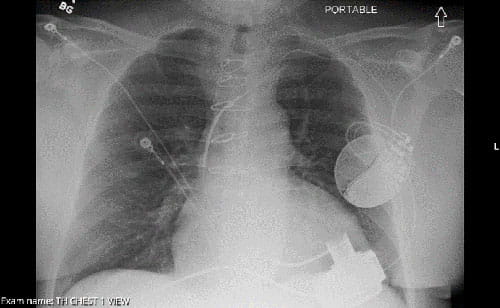

This decision, paired with advancements in left ventricular assist devices (LVADs), has had a dramatic impact on survival for patients, says Michael Zacharias, DO, Medical Director of Mechanical Circulatory Support Program and Director, Inpatient Cardiovascular Service at University Hospitals Cleveland Medical Center, and Assistant Professor at Case Western Reserve University School of Medicine. Now, he says, certain cardiogenic shock survivors who may have faced just 50-50 odds of survival may now expect to live five to 10 years, if not longer, with an LVAD.

Next, the Shock Team evaluates whether the patient is a good candidate for an LVAD. The decision-making about potential LVAD therapy is multifactorial, Dr. Zacharias says. “The ones we consider for LVAD therapy are those who cannot come off of either IV medicines that are supporting their heart or a temporary heart pump that was placed at the time of their diagnosis of cardiogenic shock,” he says.